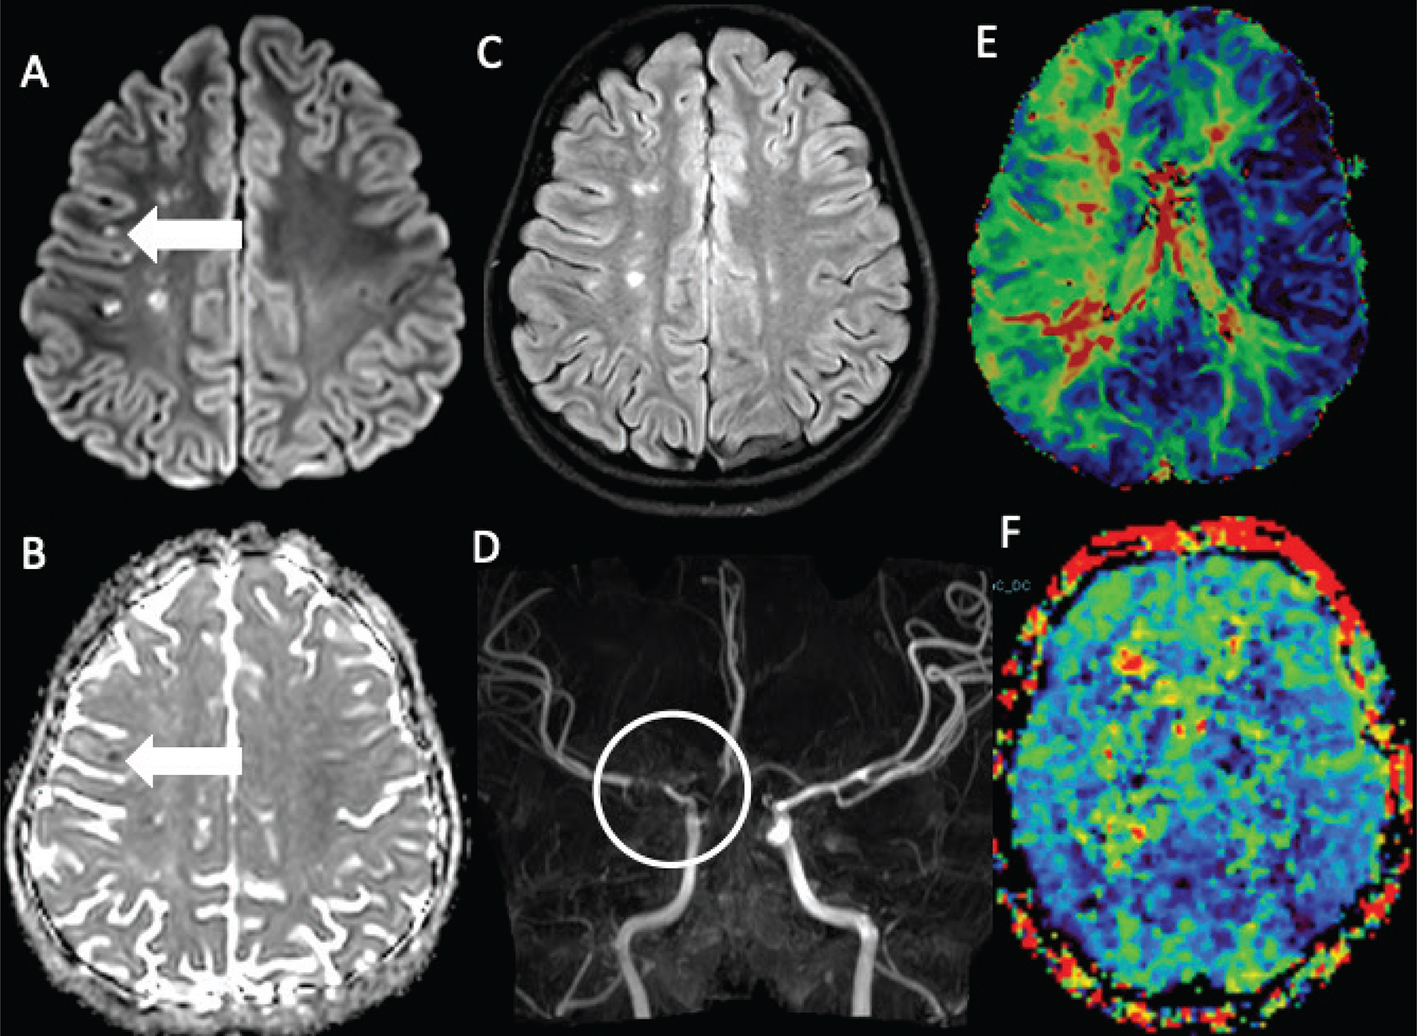

Fig 7

Figure 7. A 17-year-old female who presented with an episode of left facial droop and difficulty speaking. DWI (A) with corresponding ADC (B) and FLAIR (C) MR images demonstrate an acute infarct (arrow) in the left frontal lobe with additional remote infarcts in the bilateral frontoparietal white matter, more on the right than the left. MRA (D) demonstrates occlusion of the right ICA terminus and proximal right ACA and MCA with associated collaterals (circle). DSC perfusion mean transit time (MTT) map (E) demonstrates prolonged MTT in the right middle cerebral artery territory. MTT perfusion map after encephaloduroarteriosynangiosis (F) demonstrates improved, now symmetric transit times between cerebral hemispheres.